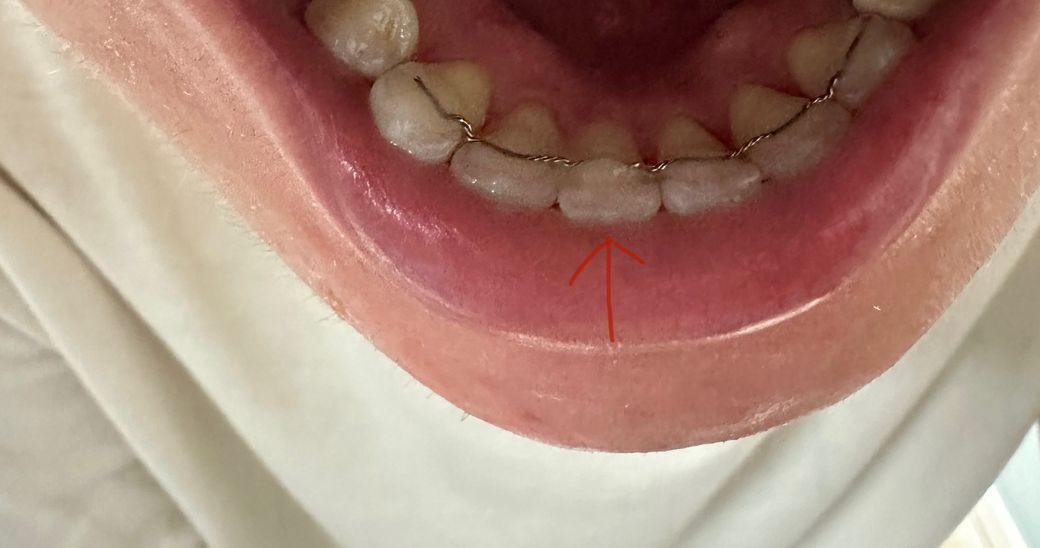

고정식유지장치 재부착했는데 사이가 치실이 안들어가져요

안녕하세요! 오늘 아래 정중앙 앞니 두개중 하나에 유지장치가 벌어져서 몇년전 교정마친 치과에서 재부착을 처음 받았는데 집에와서 양치하려 보니 치실이 안들어가져서 놀래서 거울을 봤는데 잇몸사이로 레진이 보여요.. 이거 원래 이렇게 부착하는건가요..?

• 1번 째 사진

지금 사진으로서는 해당 부분의 레진을 열어주는 것이 좋을 수 있어 보이나 고정유지장치를 낄 당시의 치아 상태에 따라 현재 상태로 레진을 했는 이유가 있을 수도 있어 보입니다. 계속해서 불편감이 있거나 의문이 있다면 교정치과 방문 후 해당 부분에 대한 검사를 해보고 상담을 해보시는 것이 좋아 보입니다.